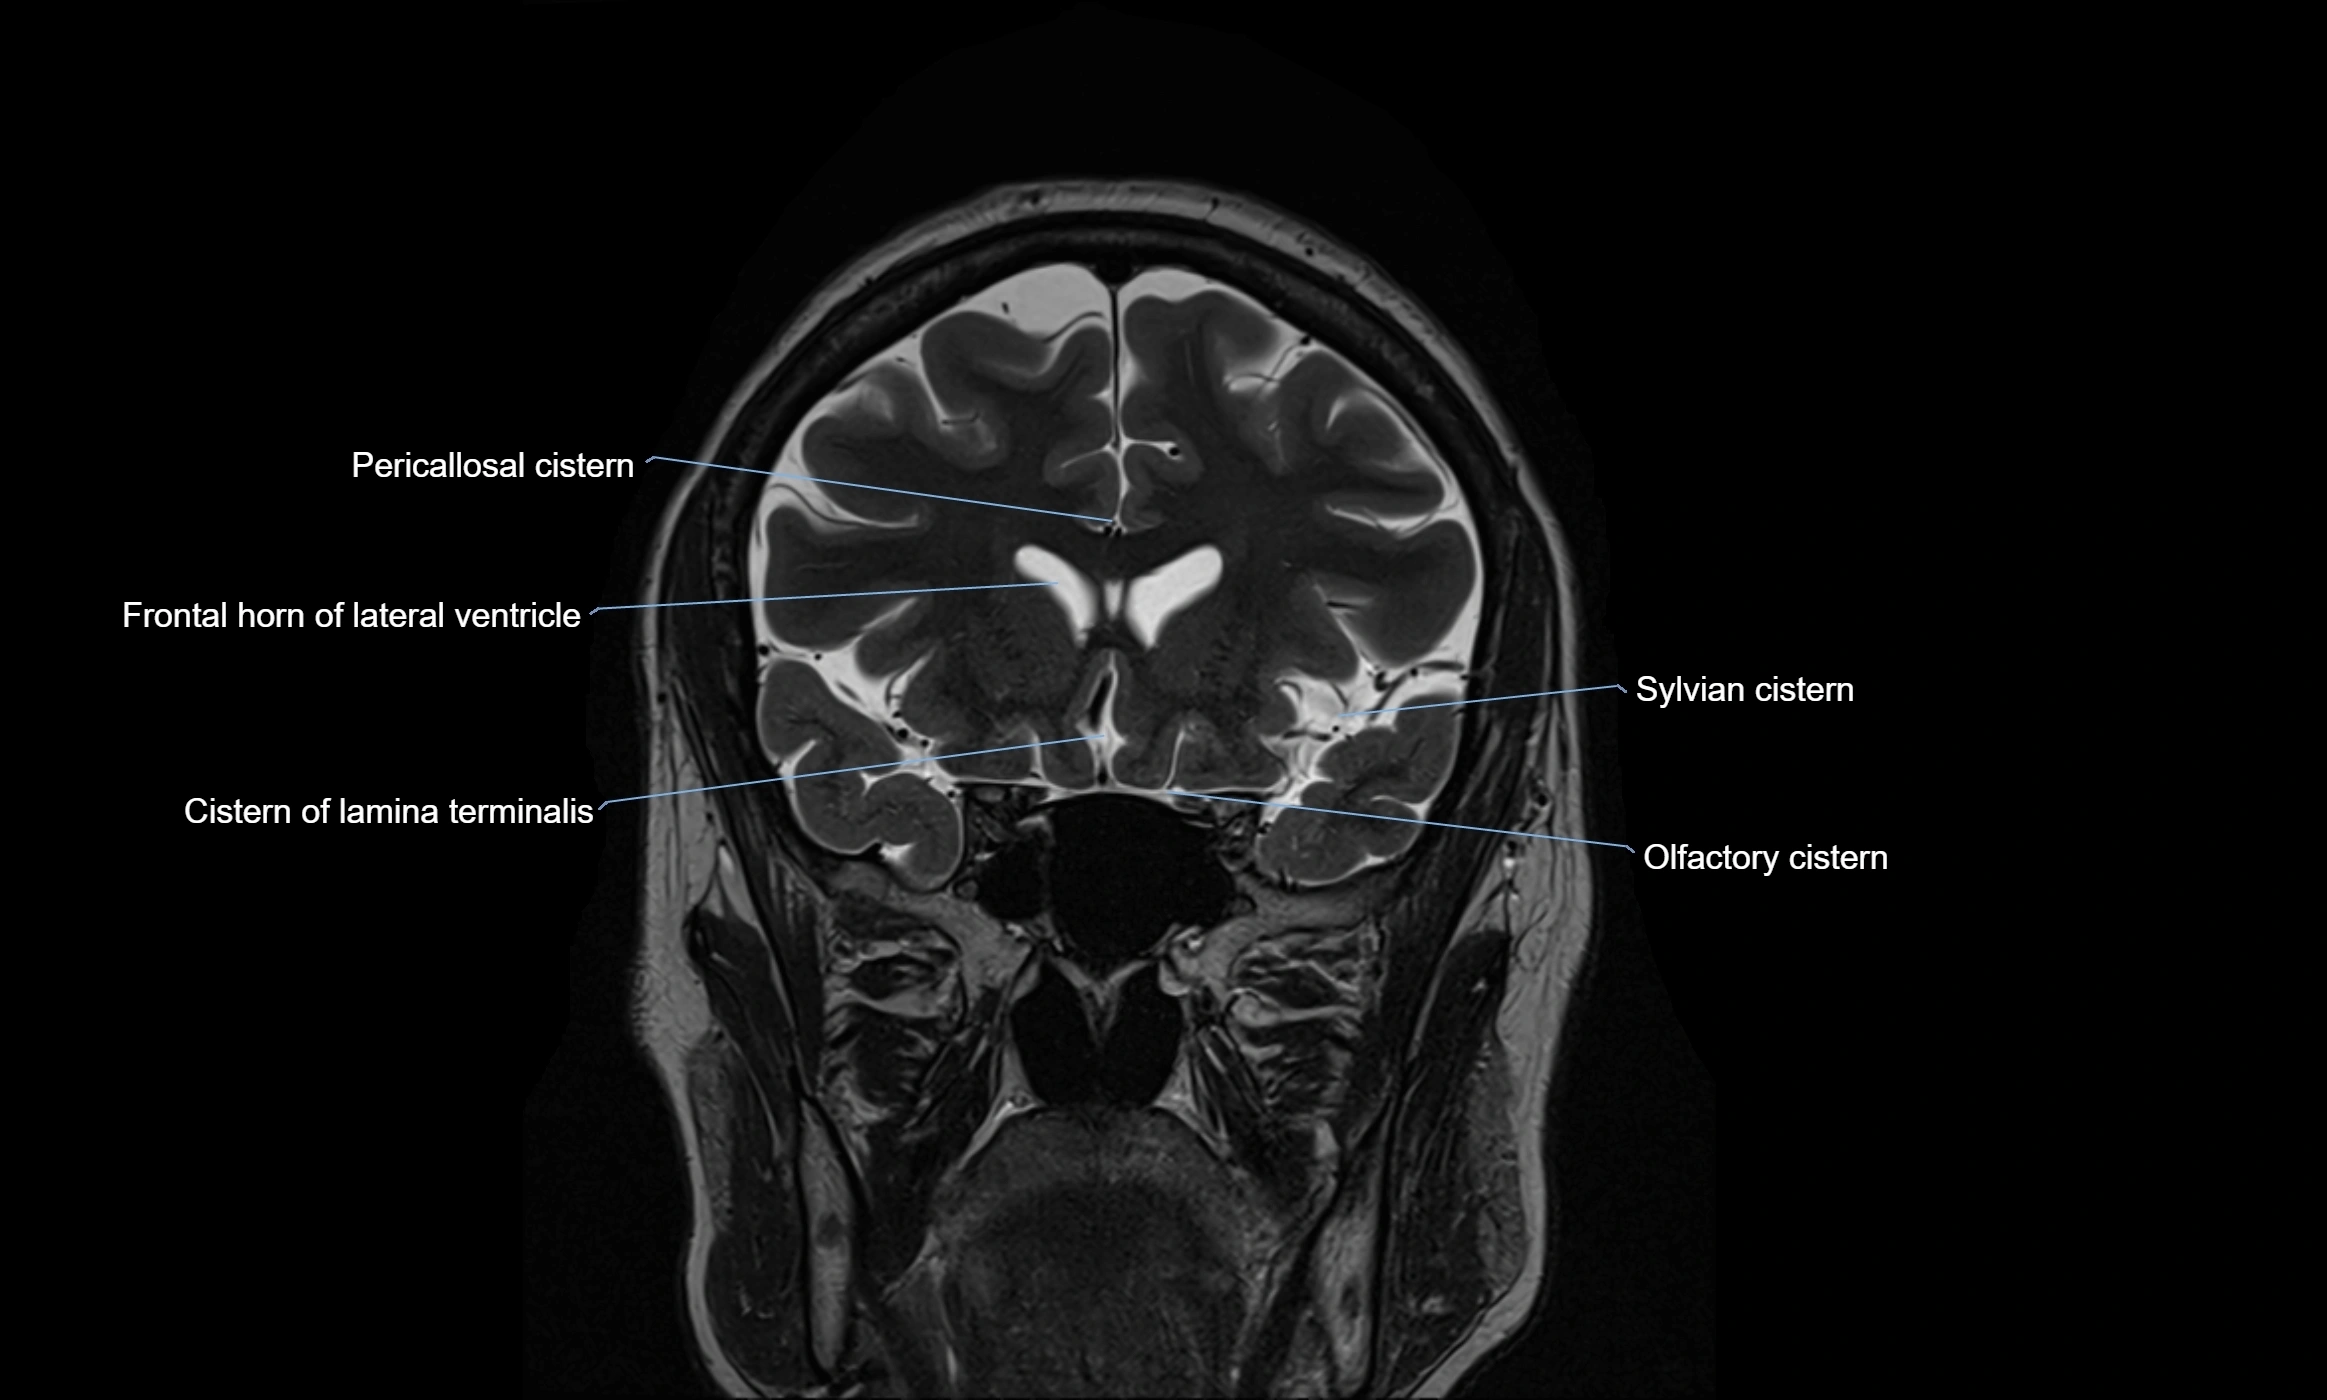

MRI images

image